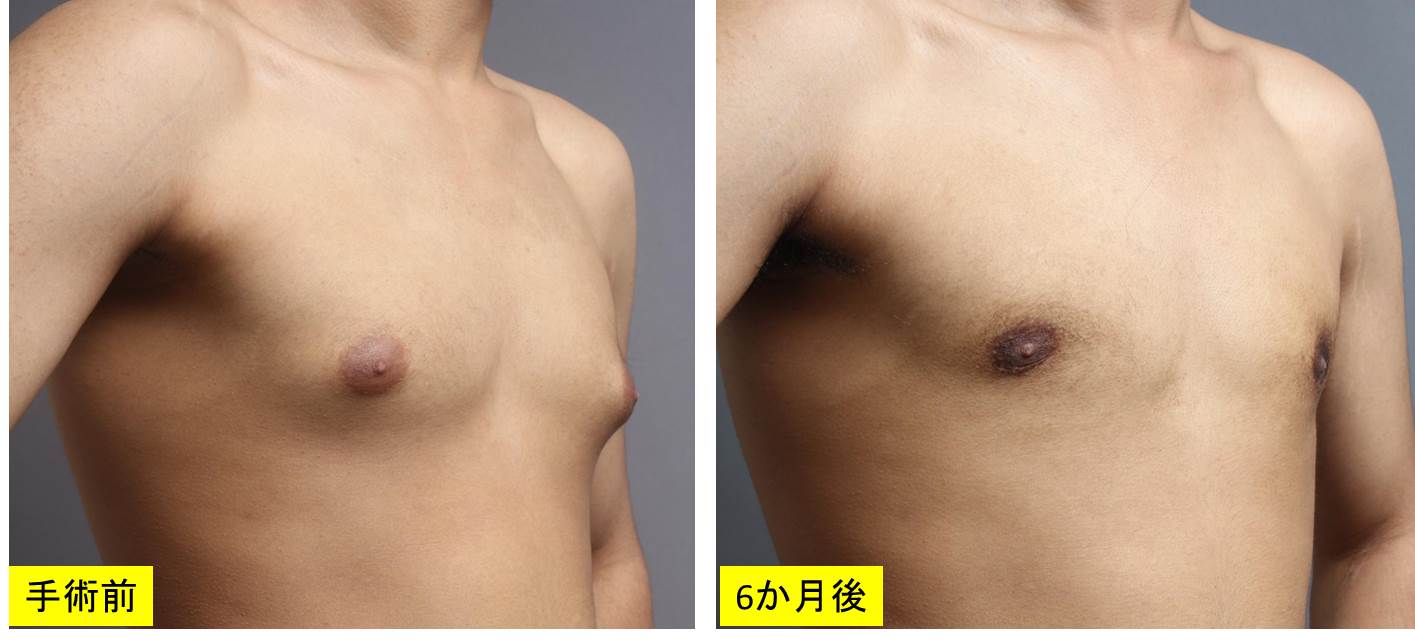

女性化乳房治療後6ヵ月の様子